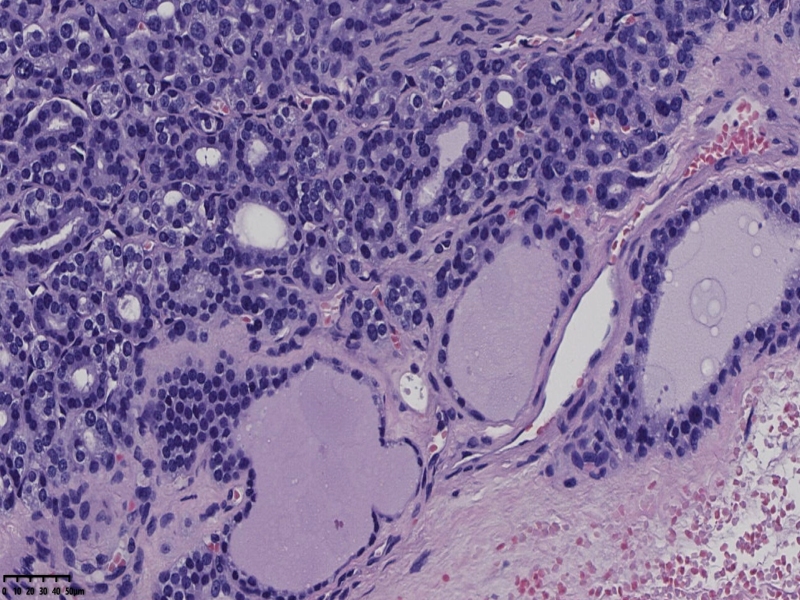

男、69、甲状腺左叶肿物,部分为囊性,囊内可见乳头状结构,上皮核重叠,没有核沟,没有毛玻璃样改变,没有核内假包涵体。255427

部分区域瘤组织与周围甲状腺组织分界明显,没有包膜样结构,滤泡结构为主,细胞异型明显。